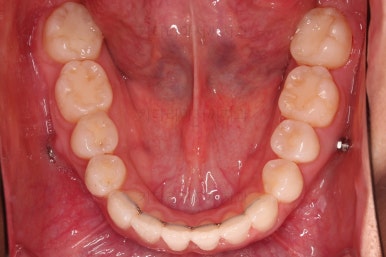

종료 시 사진입니다.

중앙선, 교합, 치아배열 모습 모두 양호해졌습니다.

부산교정잘하는치과 전후 비교해 보겠습니다.

치열도 당연히 좋아졌지만 웃을 때 보이는 치열도 매우 예뻐졌습니다.

입매도 본인이 원하는 수준으로 딱 멈춰드렸고, 적절하게 자연스럽게 약간 들어가고 마무리가 되었습니다.

전반적으로 매우 만족하신 치료가 되었습니다.